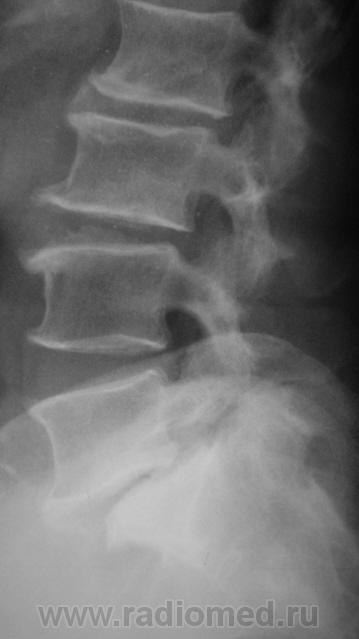

Спондилолистез L5-S1 - истинный, поэтому природа сама набедокуривши, сама и оберегает. Трудно представить безсимптомное течение, если бы это было последствием травмы. Очень рад, что Андрей Юрьевич приводит выдержки из Рейнберга. Судя по желтизне страниц - это первое издание.

По данному случаю:на мой взгляд, он является примером того, что попытки обяснить клинику(страдания пациента) только изменениями на R-граммах несостоятельны (если бы, у пациентки были жалобы,скажем на боли в области поясницы, сделали бы вывод-"что вы хотите?!-деформирующий спондилёз, да ещё спондилолистез- из-за этого и болит"). Думаю, многие сталкивались такими направлениями: "Направляеться на R-графию пояснично-крестцового отдела позвоночника.D.S.:Исключить остеохондроз ".

Спондилолистез L5-S1 - истинный, поэтому природа сама набедокуривши, сама и оберегает. Трудно представить безсимптомное течение, если бы это было последствием травмы. Очень рад, что Андрей Юрьевич приводит выдержки из Рейнберга. Судя по желтизне страниц - это первое издание